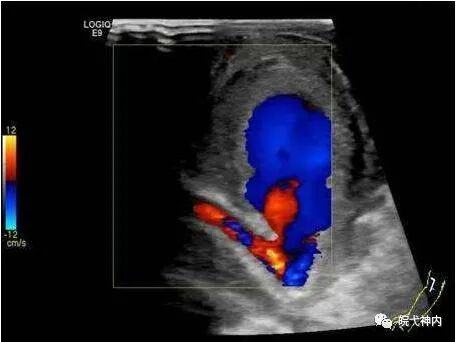

假性动脉瘤

是指经皮穿刺后血液通过动脉壁裂口进入血管周围组织并形成一个或多个瘤腔,期间可见血流进出。